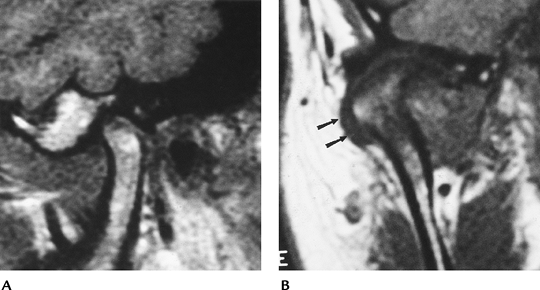

FIGURE 2-1 Normal TMJ in the sagittal (A) and coronal (B) planes.

![]() |

FIGURE 2-3 (A) Anterior disc displacement without (left) and with (right) reduction. Sagittal gradient echo (80/11, 30 degrees FA) images demonstrate a normal disc in open-mouth position (B) and an anteriorly displaced disc (arrow) (C).